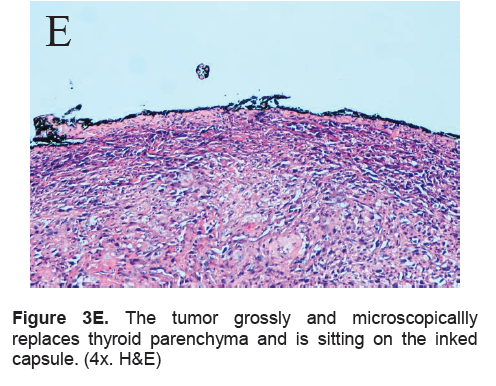

The right lobe measured 8.3 x 6.0 x 4.3 cm, and weighed 119.5 grams with a tan brown surface covered with fibrous tags (Figure 3A). Cut sections showed an ovoid mass, 6.7 x 5.2 cm in greatest dimensions, with a thin capsule and yellow-tan, gritty to mucoid cut surface with areas of hemorrhage and necrosis. The tumor infiltrated and replaced normal thyroid parenchyma and was surrounded by a thin capsular rim. Tissue sections of the right lobe revealed an infiltrative tumor composed of an admixture of pleomorphic cells, spindle cells and occasional tumor giant cells (Figure 3B). There were small areas showing reminiscent papillary or microfollicle pattern, while some areas showed large epithelioid or multinucleated tumor cells with bizarre nuclei (Figure 3C). Capsular (Figure 3D) and vascular (Figure 3F) invasion were present with extensive tumor necrosis. The uninvolved right and left lobes showed multinodular colloid goiter with lymphocytic thyroiditis. It was signed out as an Anaplastic (undifferentiated) thyroid carcinoma of the right lobe.

Click here to download Figure 3E

Figure 3E. The tumor grossly and microscopicallly replaces thyroid parenchyma and is sitting on the inked capsule. (4x. H&E)